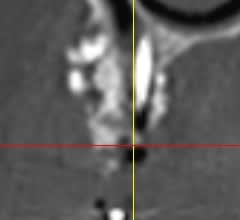

suite à divers soucis, manque d'os secteur 1, prélèvement ramique, + biooss, + vis ostéo + mbrane.

image à 6 mois

parmi les utilisateurs de biooss, avez vous déjà rencontré ce genre d'image?

et que vais je trouver ?

D'aprés ce que je vois, il semblerait qu'il n'y ait pas eu de greffe d'apposition à proprement parlé, mais utilisation d'une portion de corticale en occlusal pour maintenir le bio-oss.

Si ce que je vois à gauche est une vis, elle s'est mobilisée et tout le reste avec.

Il semblerait qu'il y ait eu , de plus, colonisation de la greffe d'une part via la vis qui transperce le sinus, et d'autres part part la dent adjacente ( image radio claire autour de cette dent).

Personnellement je pense que la greffe n'a pas fonctionnée et que ton confrère va se retrouver dans une bouillie inutilisable.